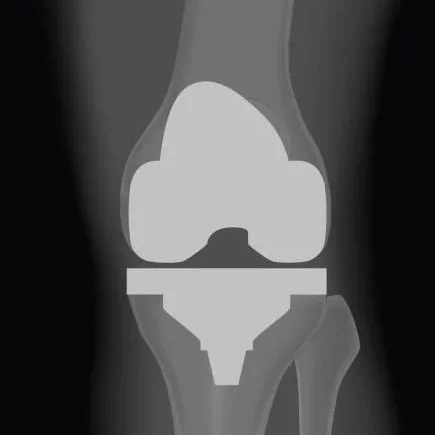

Gianluca Coccioli

ortopedico a Milano